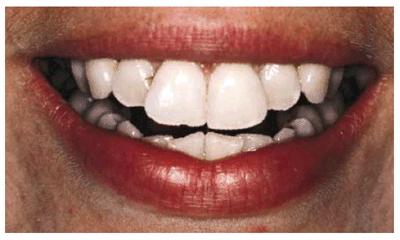

Figure 24-2A: This patient was dissatisfied with her crowded anterior teeth. Note how the gingival height differs between the central and lateral incisors.

Figure 24-2B: The dissimilar gingival heights did not bother the patient because her natural smile line concealed these irregularities.

Figure

24-2C: After a slight reproportioning of the six anterior teeth, direct

composite resin was placed and contoured (6-mm ET [Brasseler,

Figure 24-2D: The final result shows improved proportion in tooth size and form.